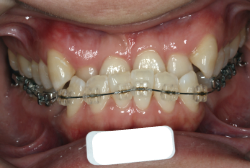

凸凹を主体としたケースの場合、当院の平均治療期間は18ヶ月ですので、このケースは少し長めに経過しました。理由の一つは凸凹の程度がかなり重症だったと言うことですが、もう一つは、右下第2大臼歯が45度くらい前傾していたため、それを整直化させるために時間を要したと考えています。いずれにしても最終結果は大変よい状態と思います。

治療前は並びが乱れて見た目が悪いというのはもちろん問題ですが、歯科医学的に一番困るのは噛み合わせが悪いという点です。上下の犬歯(3番目の歯)は、上下的に離れた位置にあるため接触することができません。つまり歯としては存在していても、歯としては機能していないということです。

凸凹の強弱とは関係なく装置を最初に付けて数日は強い不快感・疼痛がありますが、数日~2週間で慣れてきます。特にこの症例のように凸凹が厳しい場合は、凸凹の歯の表面にさらに凸凹した装置が付きますので、非常に歯が磨きにくくなり虫歯や歯周病のリスクが高まりますので、歯磨き指導を十分に受けて、セルフメンテナンスに努めることが重要です。

本症例のように前歯部の凸凹が強い場合、歯間部歯肉が痩せて退縮する場合があります(ブラックトライアングル)。またマルチブラケット法全般に言えることは、口腔粘膜の違和感、金属アレルギー、歯根吸収などのリスクがありますので、事前に担当医より詳しい説明を受けて下さい。